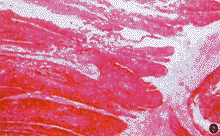

患者男,60岁。1993年8月因左眼溢泪,无脓,曾在当地医院以“慢性泪囊炎”行左泪道探通术,术后溢泪症状好转。半个月后,左泪囊部皮肤红、肿、疼痛,未扪及肿物,诊断为急性泪囊炎,予以抗生素治疗症状好转。以后曾反复发作2次,均以抗生素治疗。1996年10月24日,左泪囊区皮肤红、肿,硬结,局部压痛、无热,来我院就诊,仍按急性泪囊炎予以热敷,局部湿敷雷夫诺尔及0.25%氯霉素眼液滴眼。20天后,左泪囊区呈高度肿胀隆起,皮肤呈紫红色、表面光滑、质地较硬。泪囊X线平片示粘膜肥厚,未见骨壁破坏,按急性泪囊炎行泪囊切开术排脓,术中仅见极少量脓液(经培养无细菌生长),继续给予抗生素治疗。术后1周,左泪囊区皮肤可见约2.0 cm×2.0 cm×2.5 cm肿物,呈分叶状、质硬,表面皮肤破溃,中央似有波动感,左耳前淋巴结未扪及,继续口服抗生素。1996年11月29日行局部活检,病理报告:泪囊乳头状瘤,有恶变。血常规检查未见异常。因左泪囊部肿物迅速增大,于1996年12月19日入院。眼部检查:左侧内眦部肿物呈桑椹状约3.5 cm×3.5 cm×3.2 cm,质硬,表面血痂、肿物与皮肤粘连、基底不活动;视力0.8,左眼球轻度前突,结膜水肿,眼球内转、下转受限。右眼正常。给予口服头孢氨苄,每次0.25 g,每日3次,局部滴0.25%氯霉素眼液。CT检查:左眼鼻侧巨大软组织块影,界清,密度欠均匀,眼球向颞上移位,球壁受压变形、内直肌受压向颞侧移位,病变累及筛窦。1周后肿物明显增大约4.5 cm×4.5 cm×3.9 cm(图1),于1996年12月29日行泪囊肿物探查术,术中摘除肿物为7.0 cm×6.0 cm×5.0 cm,质坚硬,与皮下组织、骨壁紧密粘连,病变累及筛窦,请鼻科同时行筛窦及上颌窦肿物清除术,术中冰冻切片诊断:恶性肿瘤,切缘未见瘤细胞。术后10天拆线,出院时除左眼向下转轻度受限外,余正常。术后未行其他治疗。随访23个月,未见肿瘤复发。病理检查:光镜下示移行的上皮呈柱状增生,并形成多个乳头状结构,其内可见结缔组织芯(图2)。高倍镜下示移行的上皮细胞层次较多,细胞自基底至表层缺乏正常的分化,极性丧失。胞核大小不等,染色质集聚,有丝分裂像活跃(图3)。病理诊断:泪囊乳头状移行上皮癌。

图1 左泪囊部肿物,桑椹状,表面血痂,与皮肤粘连,不活动图2 移行上皮呈柱状增生,形成多个乳头状结构 HE×40